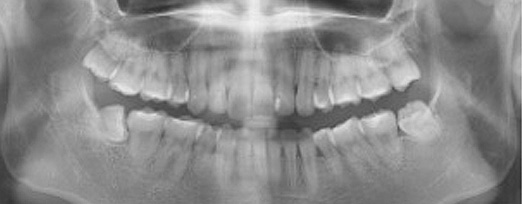

치주염 단계별 증상

건강한 상태

치아 주위의 잇몸이 핑크색을 띄며, 잇몸에서 피가 나지 않음.

스케일링을 6개월 ~ 1년 주기로 받고 올바른 칫솔질로 건강한 치주 조직을 유지

치은염 (초기~중기)

치아 주위의 잇몸이 붉게 부어 있으며, 칫솔질 등을 할 때 피가 남.

스케일링 주기의 조절이 필요할 수 있으며, 올바른 칫솔질을 시행하여야 함.

치주염 (중기~말기)

주기적으로 잇몸이 붓고 피가 나며, 욱씬하거나 우리한 통증이 나타남.

치주치료 및 정도에 따라 치주수술(잇몸수술)이 필요함. 향후 관리 정도에 따라 3~6개월 간격으로 내원하여 유지치료를 시행하여야 함.

치주염 (말기)

잇몸이 항상 부어 있으며, 이가

흔들리는 정도가 점점 심해짐.

치주치료가 필요하며, 정도에 따라 치아를 발치하여야 할 수 있음.